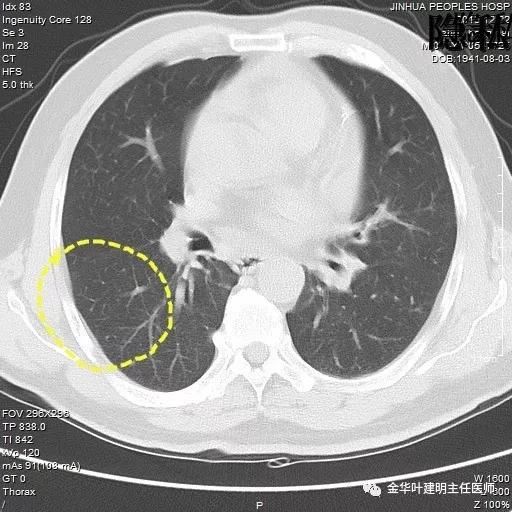

以上是2018年5月的片子,此处也呈空腔性病灶,但也点像是个肺大泡,因为绿色箭头所指处也有肺大泡。

如果我们把各个时候的片子放在一起对比,就会发现右下叶背段的空腔性病灶是从无到有,并逐渐进展的:

逐渐进展的空腔性病灶,特别边缘还是磨玻璃样的,需要特别当心,虽然有的层面看上去似肺大泡,但仍需我们提高警惕,注意必要的随访复查。